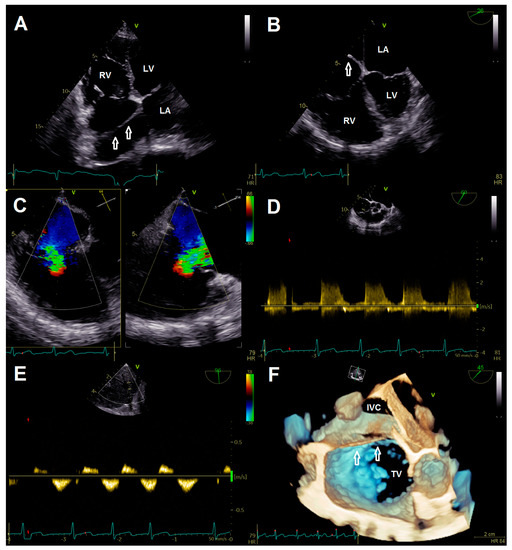

Intervention was performed with general anesthesia, using the right femoral vein as access route. First, the guiding sheath was positioned in the SVC with careful retraction during the steering maneuver of the clip delivery system (CDS) to avoid interaction with the CTD membranes. After alignment of the CDS and device according to targeted anteroseptal commissure, the first clip (TriClip® G4 XT) was implanted (Videos S11 and S12). Although re-evaluation of TR showed adequate reduction, the remaining jet was still classified as significant (Videos S13–S16). Therefore, we intended to implant two more clips centrally to the first one. Again, great care was taken to maneuver the CDS into the right ventricle by passing the membrane through its orifice (Figure 3A, Video S17). Deployment of both devices (TriClip® G4 XT) was achieved without any notable complications (Videos S18–S26). The anteroseptal commissure was sealed, resulting in bicuspidalization of the tricuspid valve and mild-to-moderate residual TR (Figure 3B, Videos S27–S29). Postprocedural echocardiography confirmed procedural results with a transvalvular mean gradient of 3 mmHg (Figure 3C), while pericardial effusion was excluded. After a few hours of uneventful observation at the intensive care unit, the patient was transferred to the normal ward. She was discharged with improved symptoms on the fourth postoperative day.

Figure 3. (A) Crossing of membrane (arrows) during introduction of the clip delivery system. (B) Multiplane color doppler evaluation of tricuspid regurgitation after implantation of three clips. (C) Continuous wave doppler after clip implantation showing no relevant tricuspid stenosis. Abbreviations: AV, aortic valve; CDS, clip delivery system; LA, left atrium; TC, TriClip®; TV, tricuspid valve.